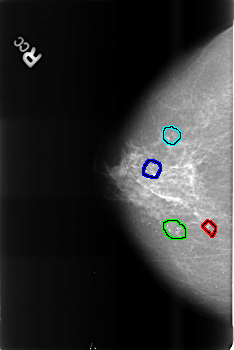

FILE: B_3472_1.RIGHT_MLO.OVERLAY

TOTAL_ABNORMALITIES 3

ABNORMALITY 1

LESION_TYPE CALCIFICATION TYPE PLEOMORPHIC DISTRIBUTION CLUSTERED

ASSESSMENT 2

SUBTLETY 4

PATHOLOGY BENIGN_WITHOUT_CALLBACK

ABNORMALITY 2

ABNORMALITY 3